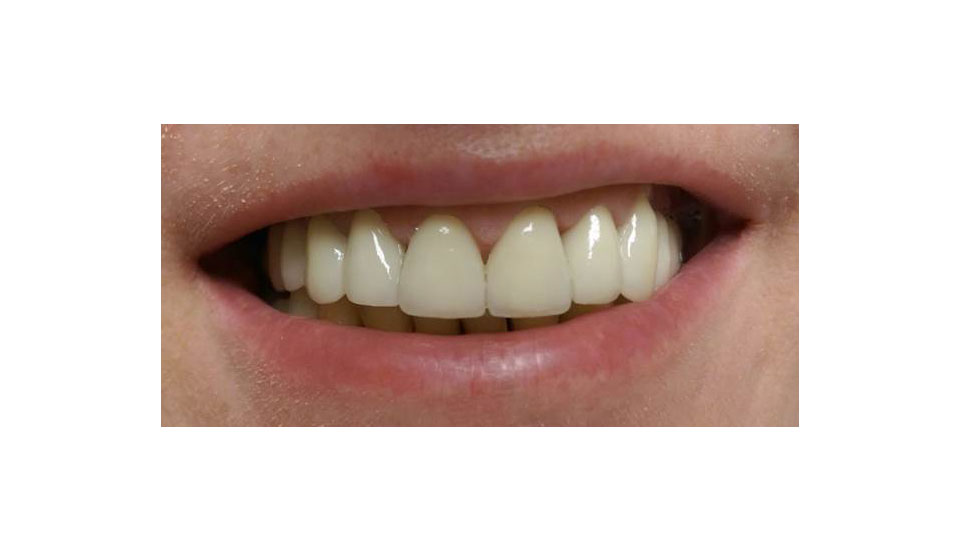

Páciens #1 utána:

felső frontrégió esztétikai helyreállítása fémmentes cirkónium koronákkal